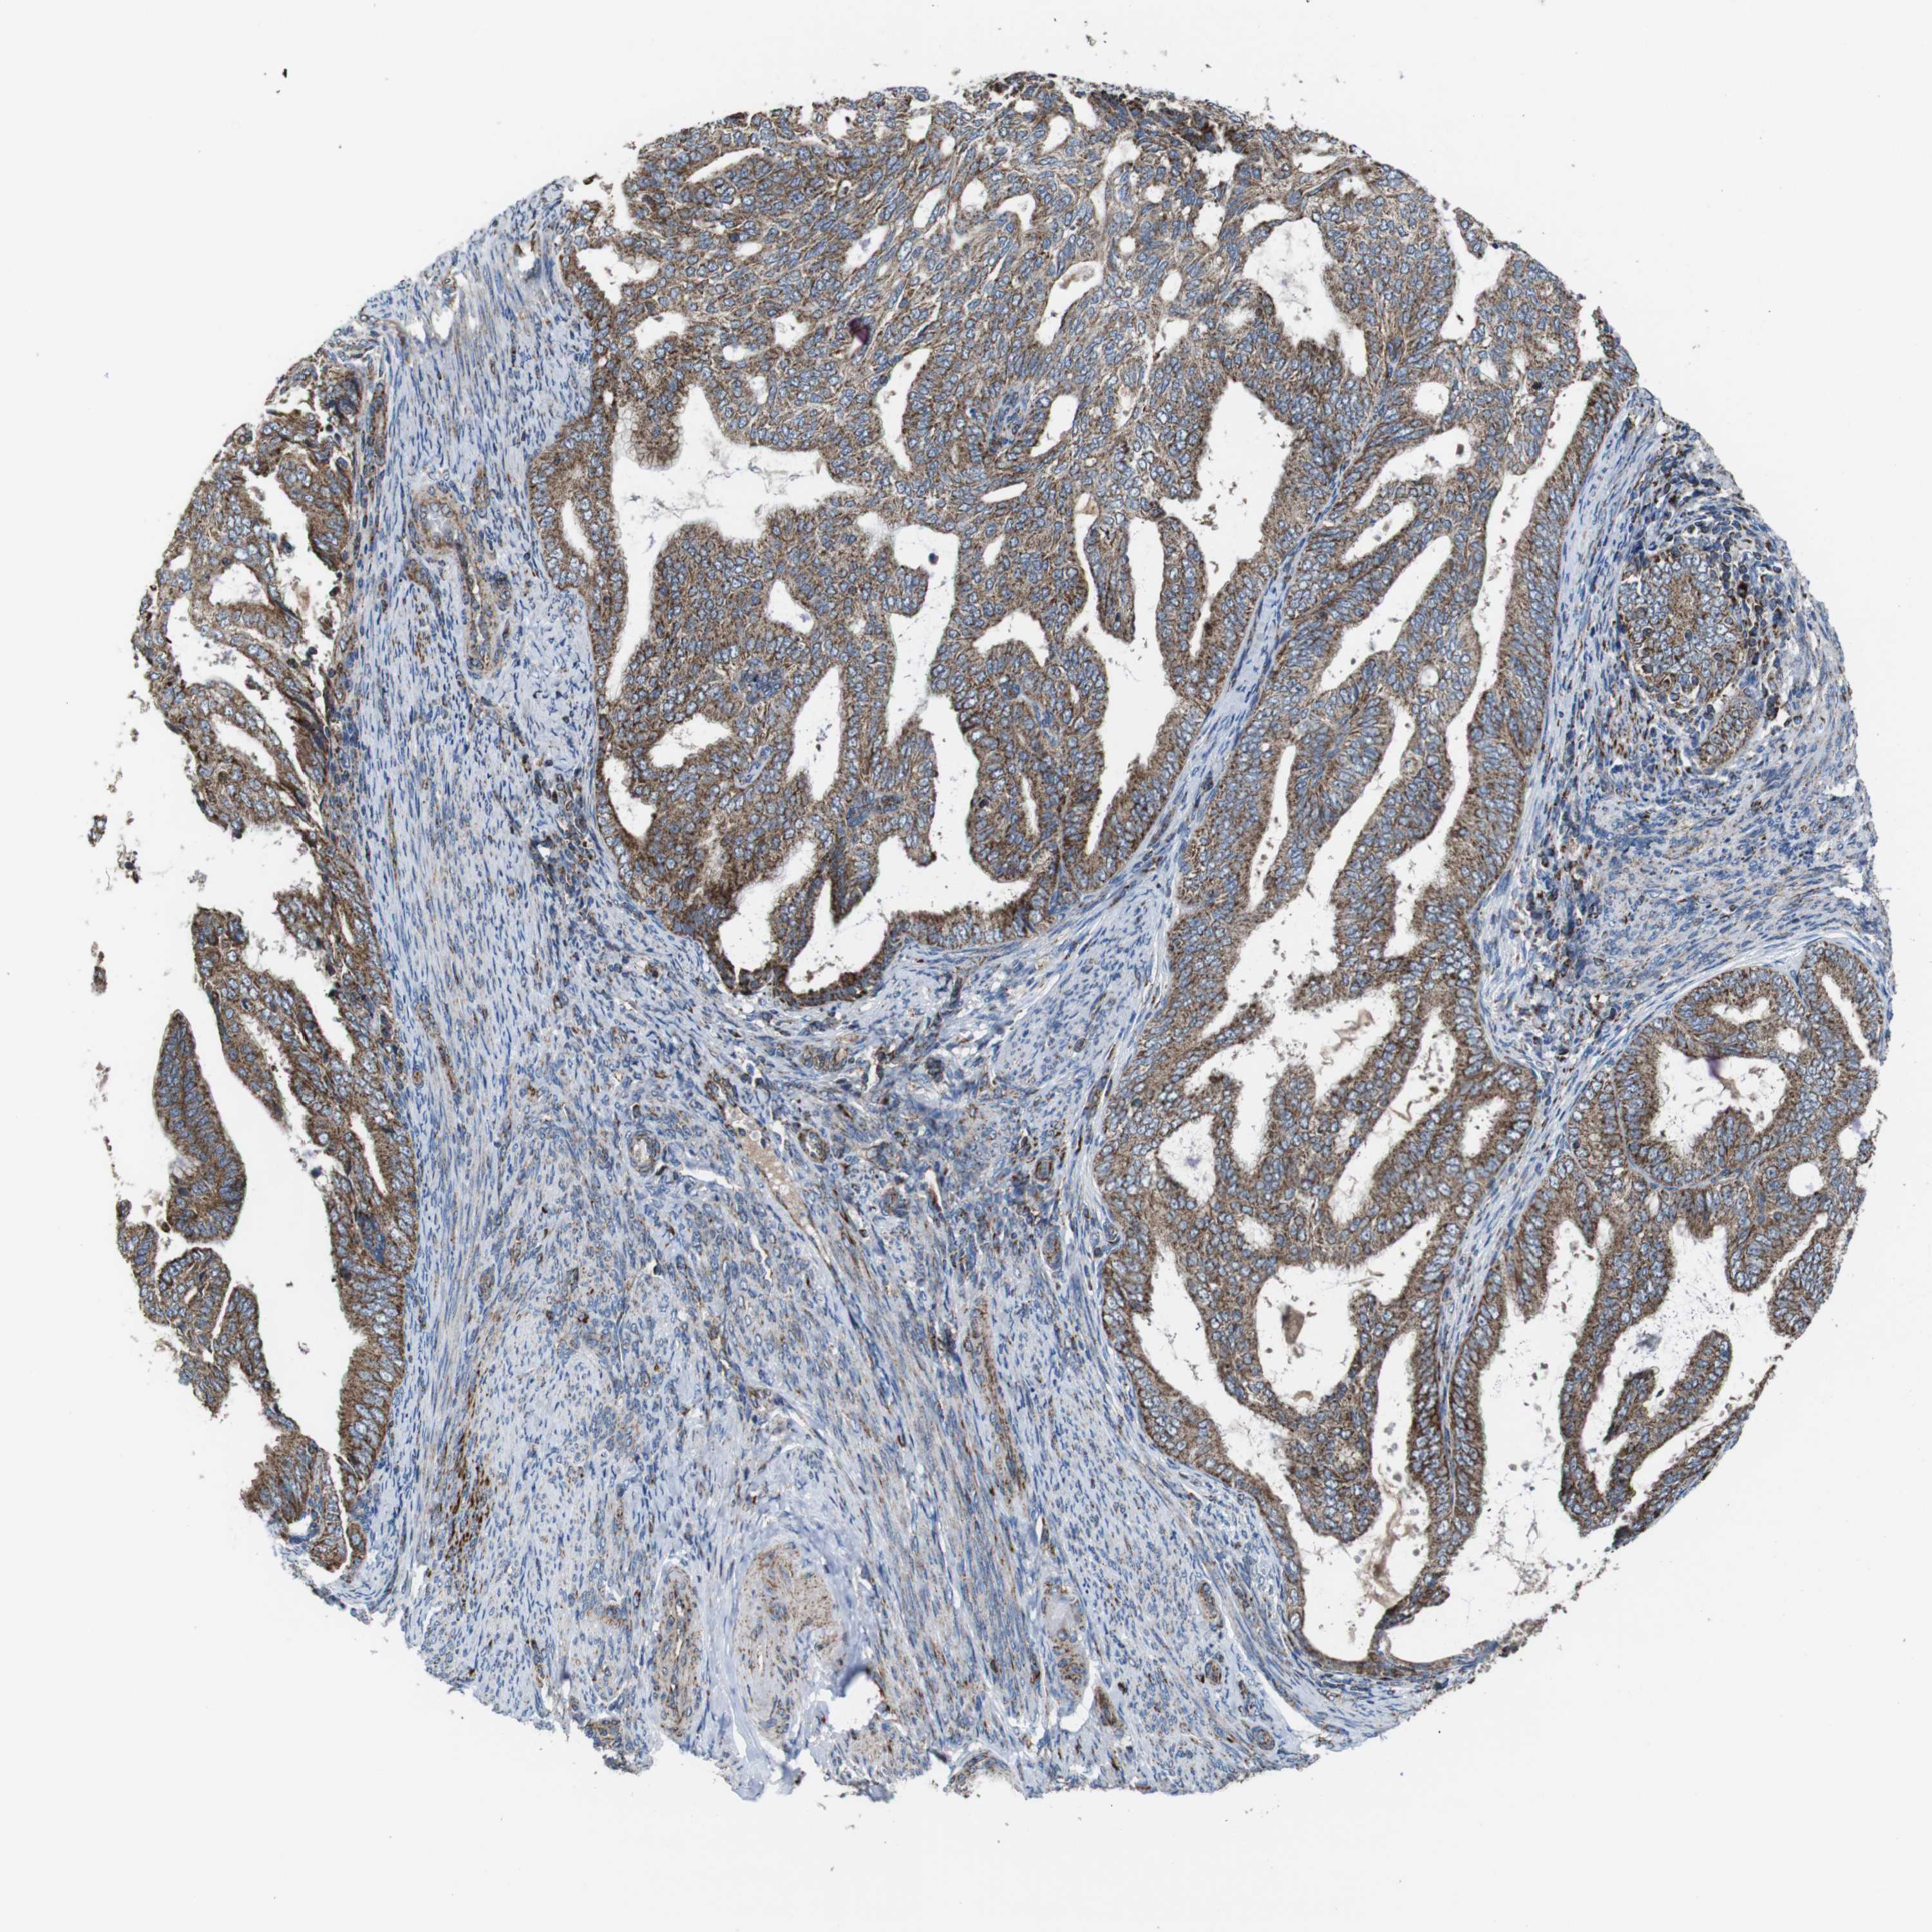

ENDOMETRIAL CANCER - Protein expressioni

A mouse-over function shows sample information and annotation data. Click on an image to view it in a full screen mode. Samples can be filtered based on level of antibody staining by selecting one or several of the following categories: high, medium, low and not detected. The assay and annotation is described here.

Note that samples used for immunohistochemistry by the Human Protein Atlas do not correspond to samples in the TCGA dataset.

Antibody stainingi

Antibody staining in the annotated cell types in the current human tissue is reported as not detected, low, medium, or high, based on conventional immunohistochemistry profiling in selected tissues. This score is based on the combination of the staining intensity and fraction of stained cells.

Each image is clickable and will lead to virtual microscopy that enables deeper exploration of all samples and also displays staining intensity scores, fraction scores and subcellular localization as well as patient and tissue information for each sample.

Antibody HPA007043

Antibody HPA007044

Antibody CAB010052

Staining

High

Medium

Low

Not detected

Intensity

Strong

Moderate

Weak

Negative

Quantity

>75%

75%-25%

<25%

None

Location

Nuclear

Cytoplasmic/membranous

Cytoplasmic/membranous,nuclear

Adenocarcinoma, NOS